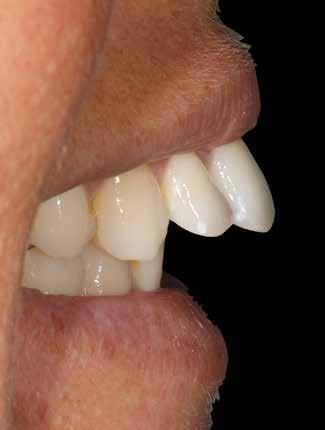

A felnőtt páciensek kezelése során általában egyszerre több ellátásra szoruló elváltozást is diagnosztizálhatunk: hiányzó fogak, kopott fogazat, esetleg régi, nem megfelelő, sérült fogpótlások, rendellenes helyzetben lévő fogak stb… Ezen páciensek kezelésekkel kapcsolatos kérései mindig az esztétikai vagy a rágással kapcsolatos kívánságaik kielégítését szolgálja. A kezelések során a fogorvosoknak nem csak a páciensek kéréseinek teljesítésére, hanem ezzel egyidejűleg a fogazat általános megjelenésének és funkciójának lehetőség szerinti javítására is törekedniük kell. Mindemellett a lehető legtöbb saját foganyag megőrzését és az évek során elvesztett kemény- és lágyrészek pótlását (pl.: hiányzó fogak, sorvadt állcsontgerinc, lágyszöveti defektusok) is szem előtt kell tartaniuk, úgy, hogy közben egy hosszú távon fenntartható eredményekkel járó kezelési tervet állítanak össze. Ezek mindig összetett esetek. Annak érdekében, hogy a fentiekben megfogalmazott összes kezelési célt teljesíteni tudjuk, interdiszciplináris megközelítésre van szükség. Az ilyen komplex rehabilitációs kezeléseket „fogászati megfiatalításnak” nevezzük. Ezeknek a beavatkozásoknak lényege az elhasználódott fogazat biológiai szempontokat figyelembe vevő minimál invazív módon történő helyreállításában rejlik, mely folyamat végére a páciensek fogai visszanyerhetik fiatalkori megjelenésüket.

A rehabilitációs kezeléseknek a célja, hogy a páciensek a lehető leghosszabb időn keresztül képesek legyenek mosolyogni és rágni. A protetikai kezeléseket végző fogorvosoknak helyre kell tudni állítaniuk a fogívek szabályos lefutását és az alsó és felső fogív között megfelelő interokkluzális érintkezéseket kell létrehozniuk. Így lehet csak az ellátás befejezését követően elért végeredmény biológiai szempontokat figyelembe vevő esztétikáját, funkcionális megfelelőségét, hosszú távú fenntarthatóságát biztosítani.

Nagyon fontos, hogy már a kezelések elején meghatározzuk, hogy melyek azok a hiányzó fogak, amelyeket a későbbiekben pótolni szeretnénk, valamint helyesen diagnosztizáljuk a kariológiai, endodonciai vagy parodontológiai okok miatt ellátást igénylő elváltozásokat. Szintén kiemelt jelentőséggel bír a fogak megtarthatóságának kiértékelése. A kezelési terv felállítása során tisztában kell lennünk azzal, hogy mely fogak alkalmasak fogpótlások ideiglenes vagy végleges elhorgonyzására.

A preprotetikai fázisban el kell látnunk a diagnosztizálásra került kórfolyamatokat, megfelelő pozícióba kell állítanunk a megtartani kívánt fogakat, pótolnunk kell az elvesztett csontállományt, valamint gondoskodnunk kell az íny megfelelő állapotáról. Ha szükség van rá, úgy a foghiányok pótlására szolgáló dentális implantátumok is ebben a fázisban kerülnek behelyezésre. Általánosságban elmondható, hogy azokat a kezeléseket, amelyek befejezése biológiai okok miatt hosszú időt vesz igénybe (pl.: fogszabályozás, csontpótlás, implantáció), a lehető leghamarabb érdemes elkezdeni.

A fogszabályzó kezelések egyik legfontosabb célja, hogy elérjük a lehető legharmonikusabb interokkluzális fogérintkezéseket, továbbá az állcsont relációs helyzetének frontális és szaggitális síkban is megfelelőnek kell lennie. A fogszabályzás befejezésekor a fogpozícióknak nem orthodonciai, hanem protetikai szempontok szerint kell ideálisnak lenniük. Az Invisalign ClinCheck szoftver (Align Technology) segítségével a protetikus az orthodontussal együtt meg tudja határozni azokat a végső fogpozíciókat, amelyek a lehető legjobb végeredmény biztosításához elengedhetetlenek. Bizonyos klinikai paramétereket, mint a fogak klinikai koronájának nagyságát, az egyes fogak fogíven belüli optimális pozícióját, a fogívek egymáshoz viszonyított helyzetét, a fogak között látható rések nagyságát, a frontfogak tengelyének dőlését, az overjet és overbite mértékét már a kezelések megkezdése előtt pontosan definiálni kell. Ezeket az adatokat viszont csak a tervezett végleges fogpótlás ismeretében lehet meghatározni, ezért van szükség az orthodontus és a protetikus szoros együttműködésére.